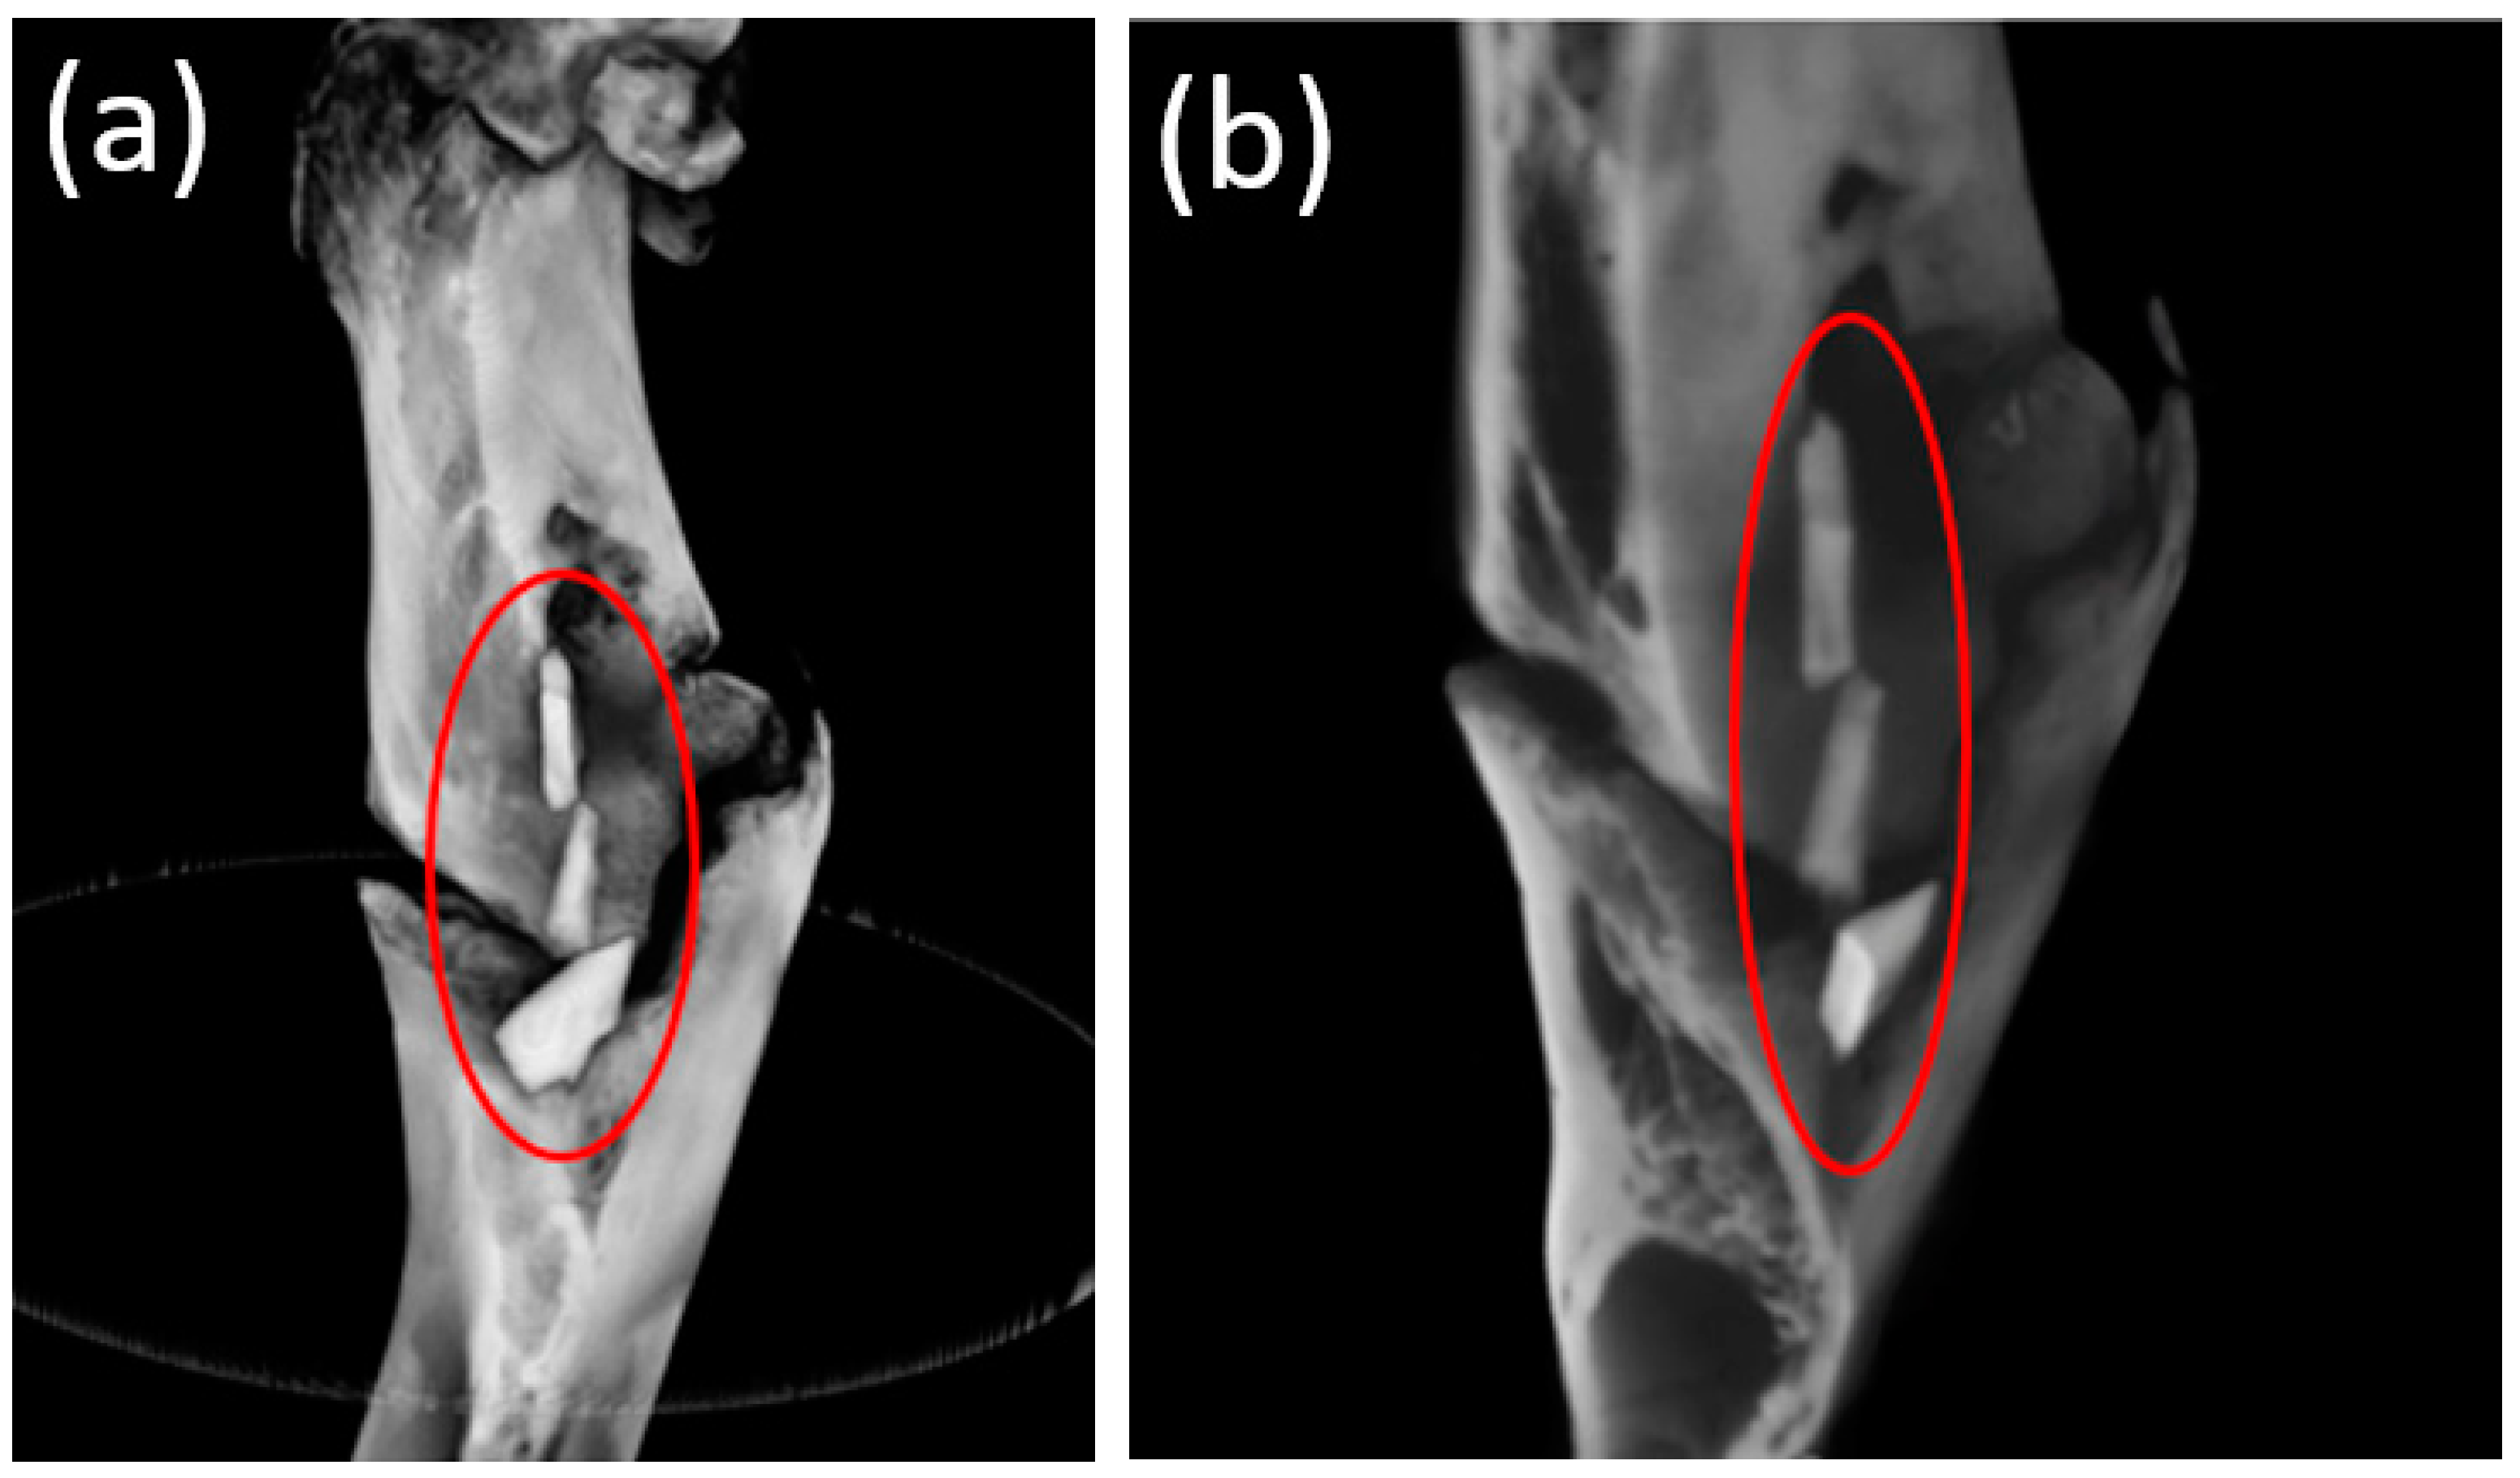

3.4. Cone Beam Computed Tomography

3.5. Micro-CT

| Diameter, mm | Length, mm | Resorption, % | Resorption Rate, mm/week | |

|---|---|---|---|---|

| Before installation | 1.70 × 1.70 × 1.70 | 5.0 | - | - |

| 1 month post-operation | 1.46 × 1.40 × 1.36 | 4.6 × 4 × 4 | 17% | 0.04 |

| 3 months post-operation | 0.7 × 1.0 × 0.8 | 3.9 × 3.7 × 3.4 | 49% | 0.09 |

| 6 months post-operation | Not rendered | Not rendered | 100% | 0.06 |